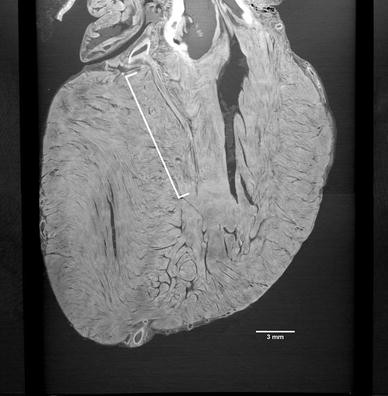

High-resolution images were obtained for all specimens. A two-dimensional slice showing the ventricular septum of a fetal heart is shown in Fig. 1. The figure clearly shows the myocardial structure and displays an inverted Y-shaped dark structure at the crest of the ventricular septum indicating the conduction bundle. The conduction bundle contains more fat tissues and appears darker in XPCT than the neighboring myocardium [7]. A video containing this slice is provided as Supplementary video 1. Figure 2 shows the left anterior descending artery and its first septal branch in the same heart. A video containing this slice is provided as Supplementary video 2. A three-dimensional volume-rendered reconstruction of the same specimen with special attention paid to the ventricular septum is provided as Supplementary video 3.

Fig. 2

XPCT image showing the first septal branch of the left anterior descending artery. Two-dimensional XPCT image of the same heart at a different angle showing the first septal branch (white bracket) originating from the left anterior descending artery